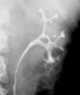

Trauma with spasm of pelvocaliceal system

Unilaterally decreased renal contrast concentration